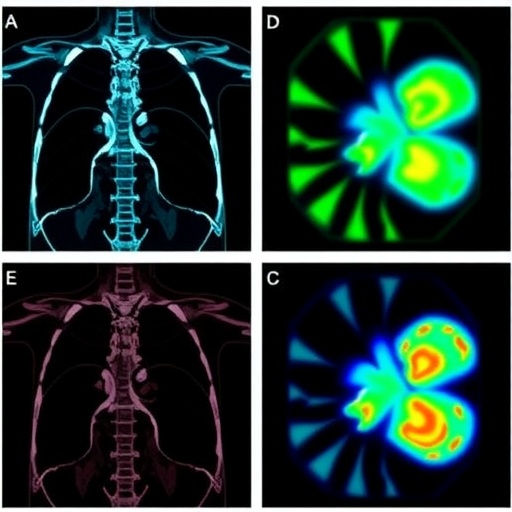

New Integrated PET Imaging Platform Quickly Identifies Clear Surgical Margins in Osteosarcoma Resection

A groundbreaking advancement in the imaging and surgical treatment of osteosarcoma promises to revolutionize how this aggressive bone cancer is...